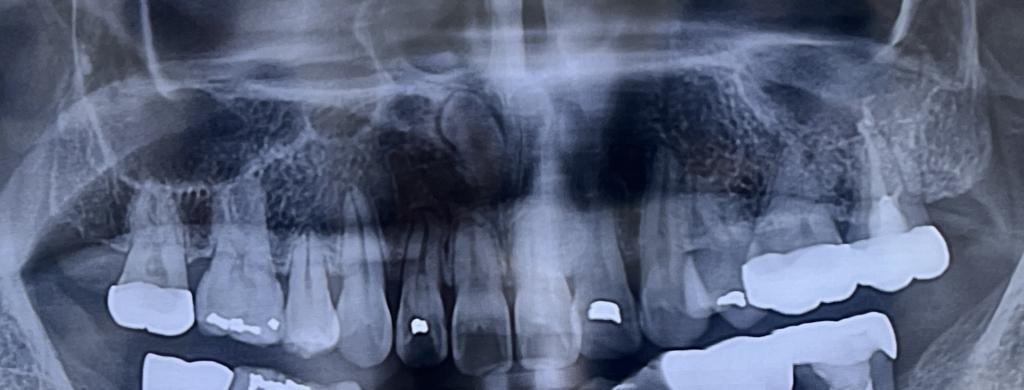

치아뿌리 움직임 봐주세요ㅜㅜ

선생님 안녕하세요~ 아이 교정 마무리 단계에서 x-ray 촬영을 하였는데 하악 왼쪽 송곳니와 상악 오른쪽 송곳니 뿌리 부분이 비스듬히 쓰러져 있더라구요 혹시 교합은 안건드리고 뿌리 부분만 바로 세우는 이동이 가...

교정마무리 한번만 봐주세요~

안녕하세요 선생님~^^ 교정을 하면서 선생님께 도움을 많이 받았습니다. 감사합니다 아이 교정이 이제 마무리가 다가 옵니다 과개교합과 왼쪽 2대구치 상.하악 가위교합으로 비발치 교정을 하였습니다 아이 치아다 보...

치아 뿌리끝이 갈고리처럼 휘었어요

(사진펑할께요~) 선생님 안녕하세요~^^ 궁금증에 대해 친절한 답변을 주셔서 감사합니다^^ 아이가 교정중에 있다보니 궁금중이 많은 엄마입니다. 파노라마 사진을 찍고보니 치아 뿌리 끝쪽이 90도로 휘어져 있어요ㅜ...